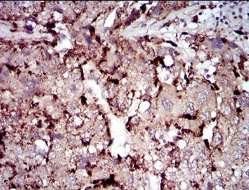

IHC    1/200 - 1/1000